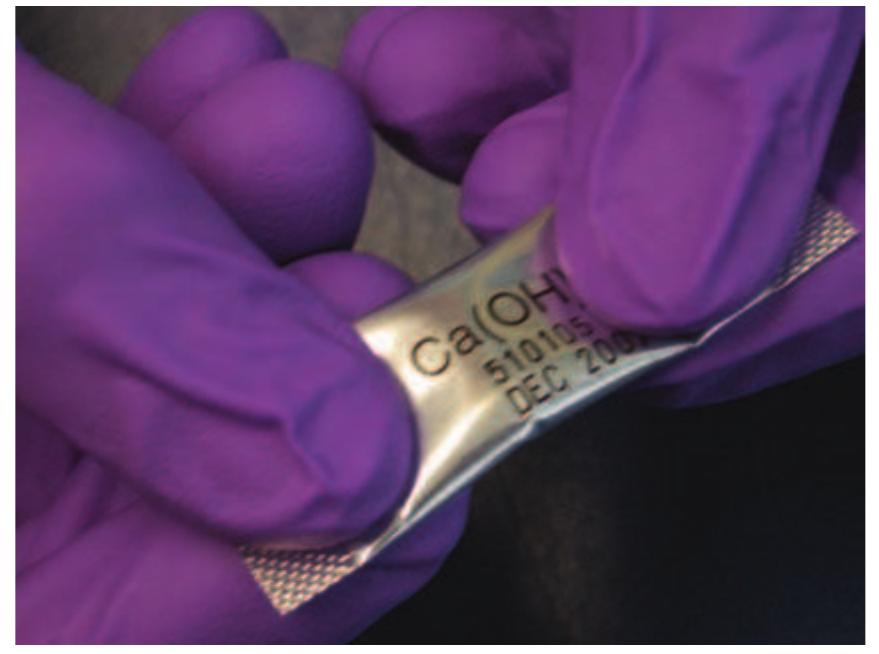

- This can then be placed into the root canal.